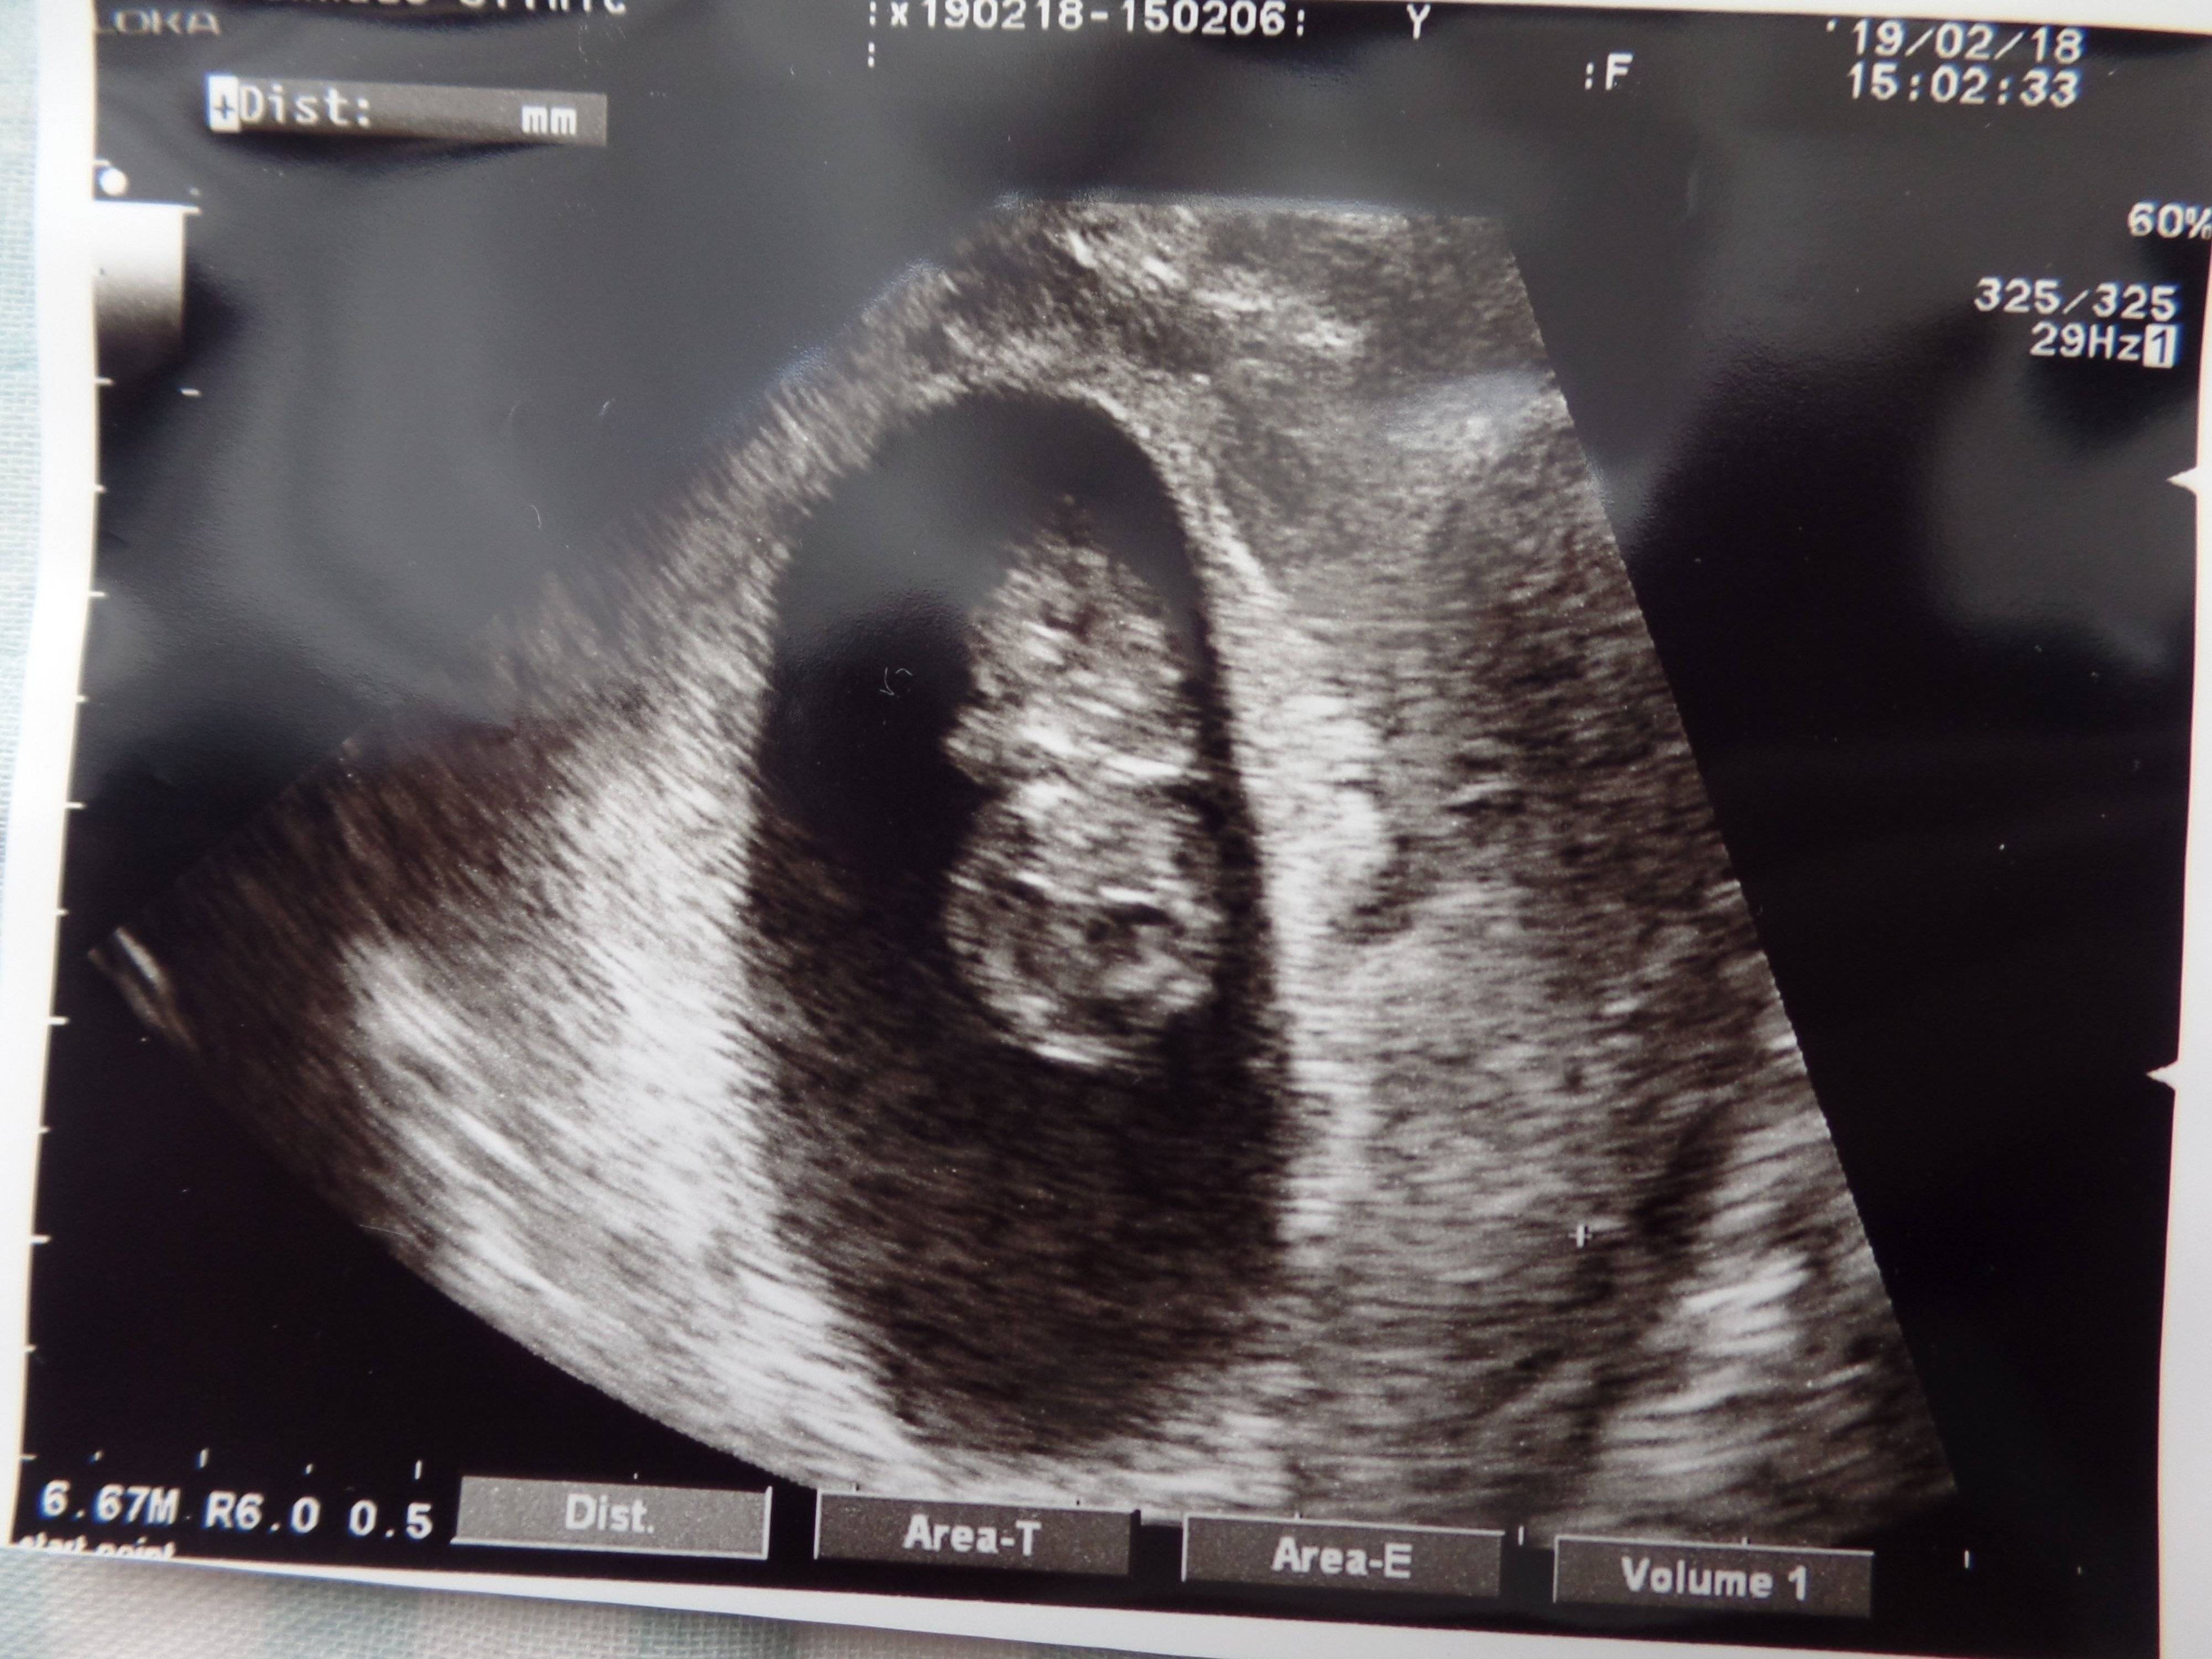

3. 多嚢胞性卵巣症候群(PCOS)から不妊治療を経て高齢出産! エコー写真で喜びを振り返る